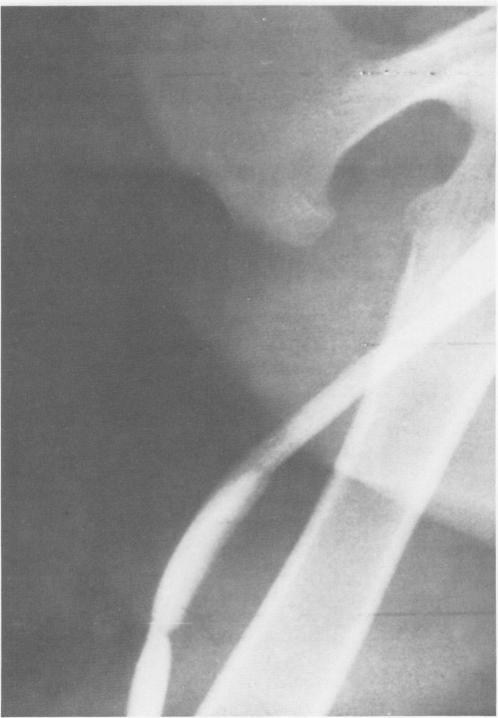

The effect of short-term treatment with aspirin or dextran on the patency of bovine heterografts in the venous system was investigated. Animals treated preoperatively and for three days postoperatively with either aspirin (600 mgm BID) or low molecular weight dextran (500 cc/day) had statistically significant increased graft patency as compared to controls during the treatment interval. Significance was lost, however, after cessation of therapy. These results suggest that either aspirin or low molecular weight dextran would be useful adjuvants to venous reconstruction. If used in the venous system, bovine heterografts might be expected to yield better short term patency with adjuvant therapy employing either dextran or aspirin.

研究了阿司匹林或右旋糖酐短期治疗对牛异种移植物在静脉系统中通畅性的影响。术前及术后三天用阿司匹林(600毫克,每日两次)或低分子量右旋糖酐(500毫升/天)治疗的动物,与对照组相比,在治疗期间移植物通畅性有统计学意义的显著增加。然而,治疗停止后,这种显著性就消失了。这些结果表明,阿司匹林或低分子量右旋糖酐将是静脉重建的有用辅助剂。如果用于静脉系统,预计牛异种移植物在采用右旋糖酐或阿司匹林的辅助治疗下可能会有更好的短期通畅性。